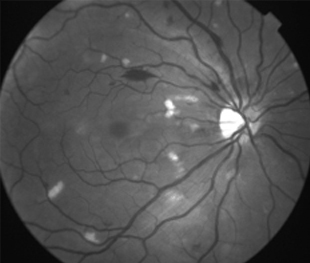

Angiografía OD

2 meses: disminución de manchas algodonosas y hemorragias con mejoría de circulación

Angiopatía retiniana traumática con manchas algodonosas, extravasación linfática después de aumento de presión intracraniana.

- Bilateral, 20/200 a CD, alteración de la capa de fibras nerviosas, atrofía disco óptico.

- Angiografía: teñido arterial, escape capilar, más tardíamente, no perfusion arteriolar y venular con teñido de las paredes vasculares y dilatación venosa.